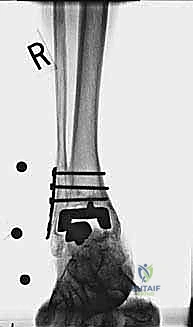

- الأشعة السينية مع تحميل الوزن (Weight-bearing X-rays): لتقييم الزوايا الميكانيكية وتحديد مدى هبوط المفصل أو وجود كسور في الكعب.

من أعقد التحديات التي تواجه جراحي العظام هي حدوث كسور في الكعب الداخلي (Medial Malleolus) أو الخارجي (Lateral Malleolus) في وجود مفصل صناعي. تحدث هذه الكسور لعدة أسباب:

علاج هذه الكسور يتطلب مهارة فائقة من الدكتور محمد هطيف، حيث يتم استخدام تقنيات الجراحة الميكروسكوبية وتثبيت الكسور باستخدام صفائح معدنية دقيقة ومسامير (Locking Plates) دون المساس بثبات المفصل الصناعي، أو يتم دمج علاج الكسر ضمن عملية مراجعة المفصل الكلية إذا كان المفصل نفسه تالفاً.

يتم إدخال المفصل الجديد المخصص للمراجعة، والذي يحتوي غالباً على سيقان (Stems) تدخل عميقاً في عظمة الساق وعظمة الكاحل لضمان الثبات الميكانيكي. في حال وجود كسور في الكعب، يتم تثبيتها في هذه المرحلة.